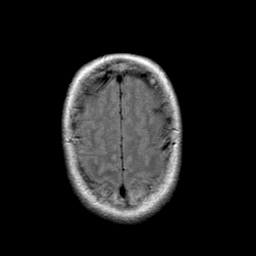

Stroke: proton density-weighted MR #1 -- Slice #21

[Home][Help][Clinical] Slice 21